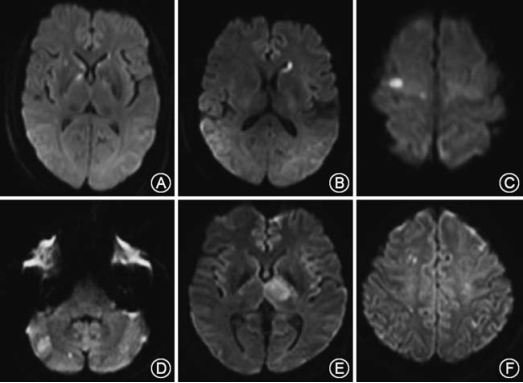

颅脑MRI示:左侧内囊后肢、苍白球稍长T1、长T2信号,DWI高信号。MRA未见血管狭窄(见图1)。

图1

颅脑DWI示:右侧内囊后肢、右侧苍白球、放射冠脑室旁后部梗死(见图3)。

图3

颅脑DWI示:右侧颞叶内侧、外侧膝状体和内囊梗死(图4)。

图4

该患者临床表现为偏瘫和偏身感觉障碍,病灶位于内囊后肢和苍白球内侧部,符合AChA供应(图5)。

图5